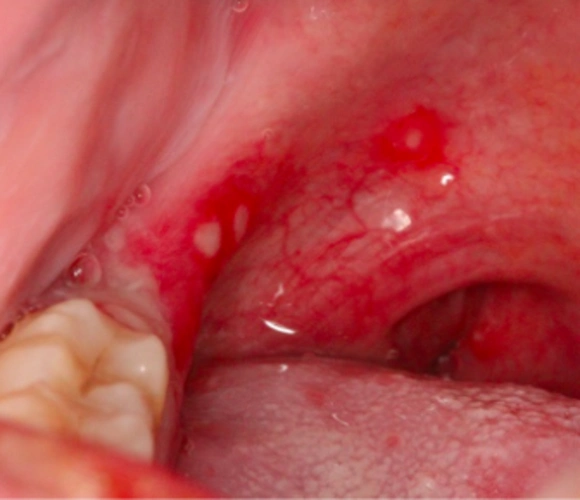

口腔疱疹图

罕见的口腔疱疹有图片求治疗方法

口腔单纯疱疹图

也就是说口腔疱疹是一个变化过程,早期是红点,然后发展为小水泡,最后

口腔疱疹

带状疱疹起到口腔内了,这个还是比较少见的,我工作这么久了还是第一次